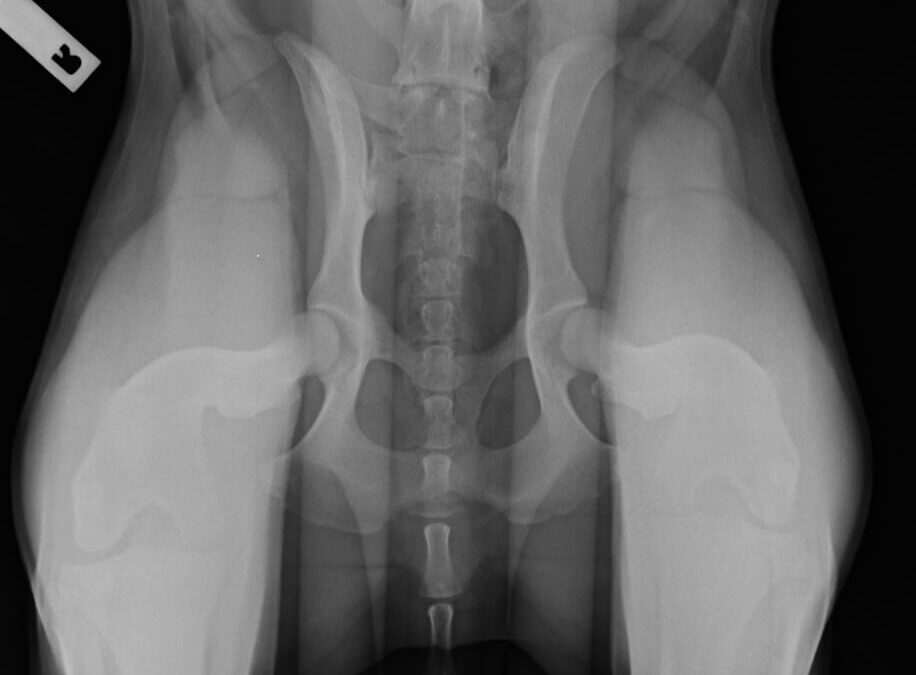

• PennHip Hip Dysplasia Screening

PennHip